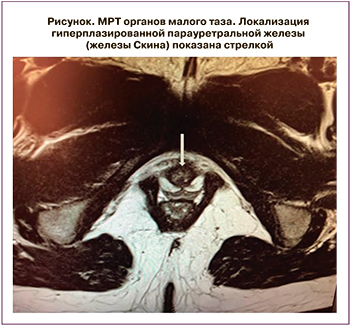

Результаты лабораторных и инструментальных обследований представлены в таблице 1. Обращало на себя внимание выраженное повышение уровней андрогенов и ренина вне приема терапии глюко- и минералокортикоидами. По результатам МРТ органов малого таза, выполненного в ходе госпитализации: признаки гипоплазии матки. Яичники: справа 2,3×1,4 см, в структуре множественные фолликулы диаметром до 9 мм; слева 2,4×2,0 см, в структуре множественные фолликулы диаметром до 8 мм. Дополнительно была верифицирована мягкотканная структура под мочевым пузырем округлой формы, неоднородной структуры, с четкими контурами, муфтообразно охватывающая проксимальные отделы уретры, размерами 2,0×1,7×2,0 см – рудиментарная ткань предстательной железы (рисунок).

Отдельного обсуждения требует обнаружение у пациентки рудиментарной парауретральной железы (или железы Скина), и дальнейшая лечебная тактика. Парауретральная железа является рудиментарным органом, гомологичным предстательной железе у мужчин и, как показано в ряде публикаций, на фоне избытка андрогенов может развиваться в ткань, гистологически идентичную мужской простате [8, 9]. Несмотря на очевидную взаимосвязь между гиперандрогенией, обусловленной адреногенитальным синдромом, и пролиферативной активностью парауретральных железистых клеток, в настоящий момент пока не изучены ключевые причины развития ее гиперплазии: на каких сроках эмбриогенеза происходит начало гиперпластических процессов, каков критический уровень андрогенов для этого, есть ли взаимосвязь с видом мутации при ВДКН [10].

Описываемое в настоящей статье клиническое наблюдение является еще одной демонстрацией столь редкого феномена развития простатоподобных клеток у пациентки с кариотипом 46, ХХ. В данном случае парауретральную железу решено было не оперировать из-за особенности топического расположения, а также из-за относительно нормального уровня простатспецифического антигена, как показателя степени гиперплазии.